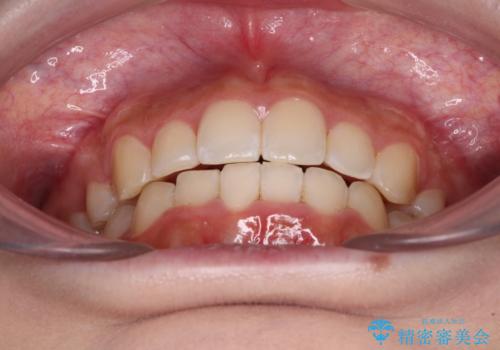

- 上顎の八重歯と、上下前歯のデコボコを気にして来院された患者様です。

奥歯の咬み合わせを見ると、上顎臼歯が下顎に対して前方にあり、叢生改善により口元が突出する顔貌ではなかったため、上顎左右第一小臼歯2本を抜歯し、ワイヤー装置にて矯正治療を行うこととしました。

前歯部のデコボコがなくなったため、歯磨きしやすくなり、非常に清潔な状態になりました。